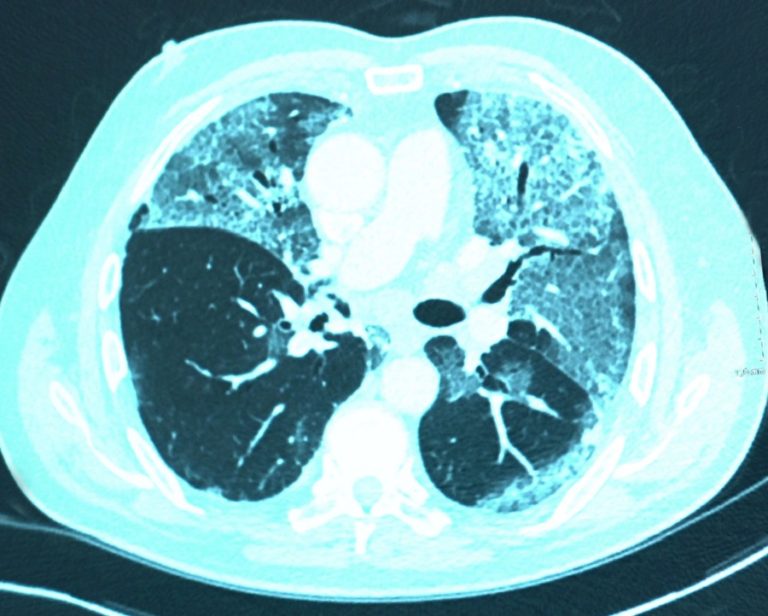

कोरोनाले फोक्सोमा दाग निम्त्याउन र समस्या उत्पन्न गर्न सक्नेमा विज्ञहरु चिन्तित रहेका छन् । कोरोनाको अवस्था अपरिवर्तनीय देखिन्छ । फोक्सामा रोग निम्त्याउन सक्ने खतरा अत्यधिक छ । यसले श्वासप्रश्वासमा समस्या सिर्जना गर्ने, कफ र थकान महसुस गराउन मुख्य भुमिका खेल्नेछ । फोक्सोमा दागलाई फेक्सो फाइब्रोसिस भनिन्छ । कोरोनाले निम्त्याउने फोक्सोको कोषिकामा दाग स्थायी रुपमा रहने कारण यसको उपचार नहुन सक्ने विज्ञहरु बताउँछन् ।